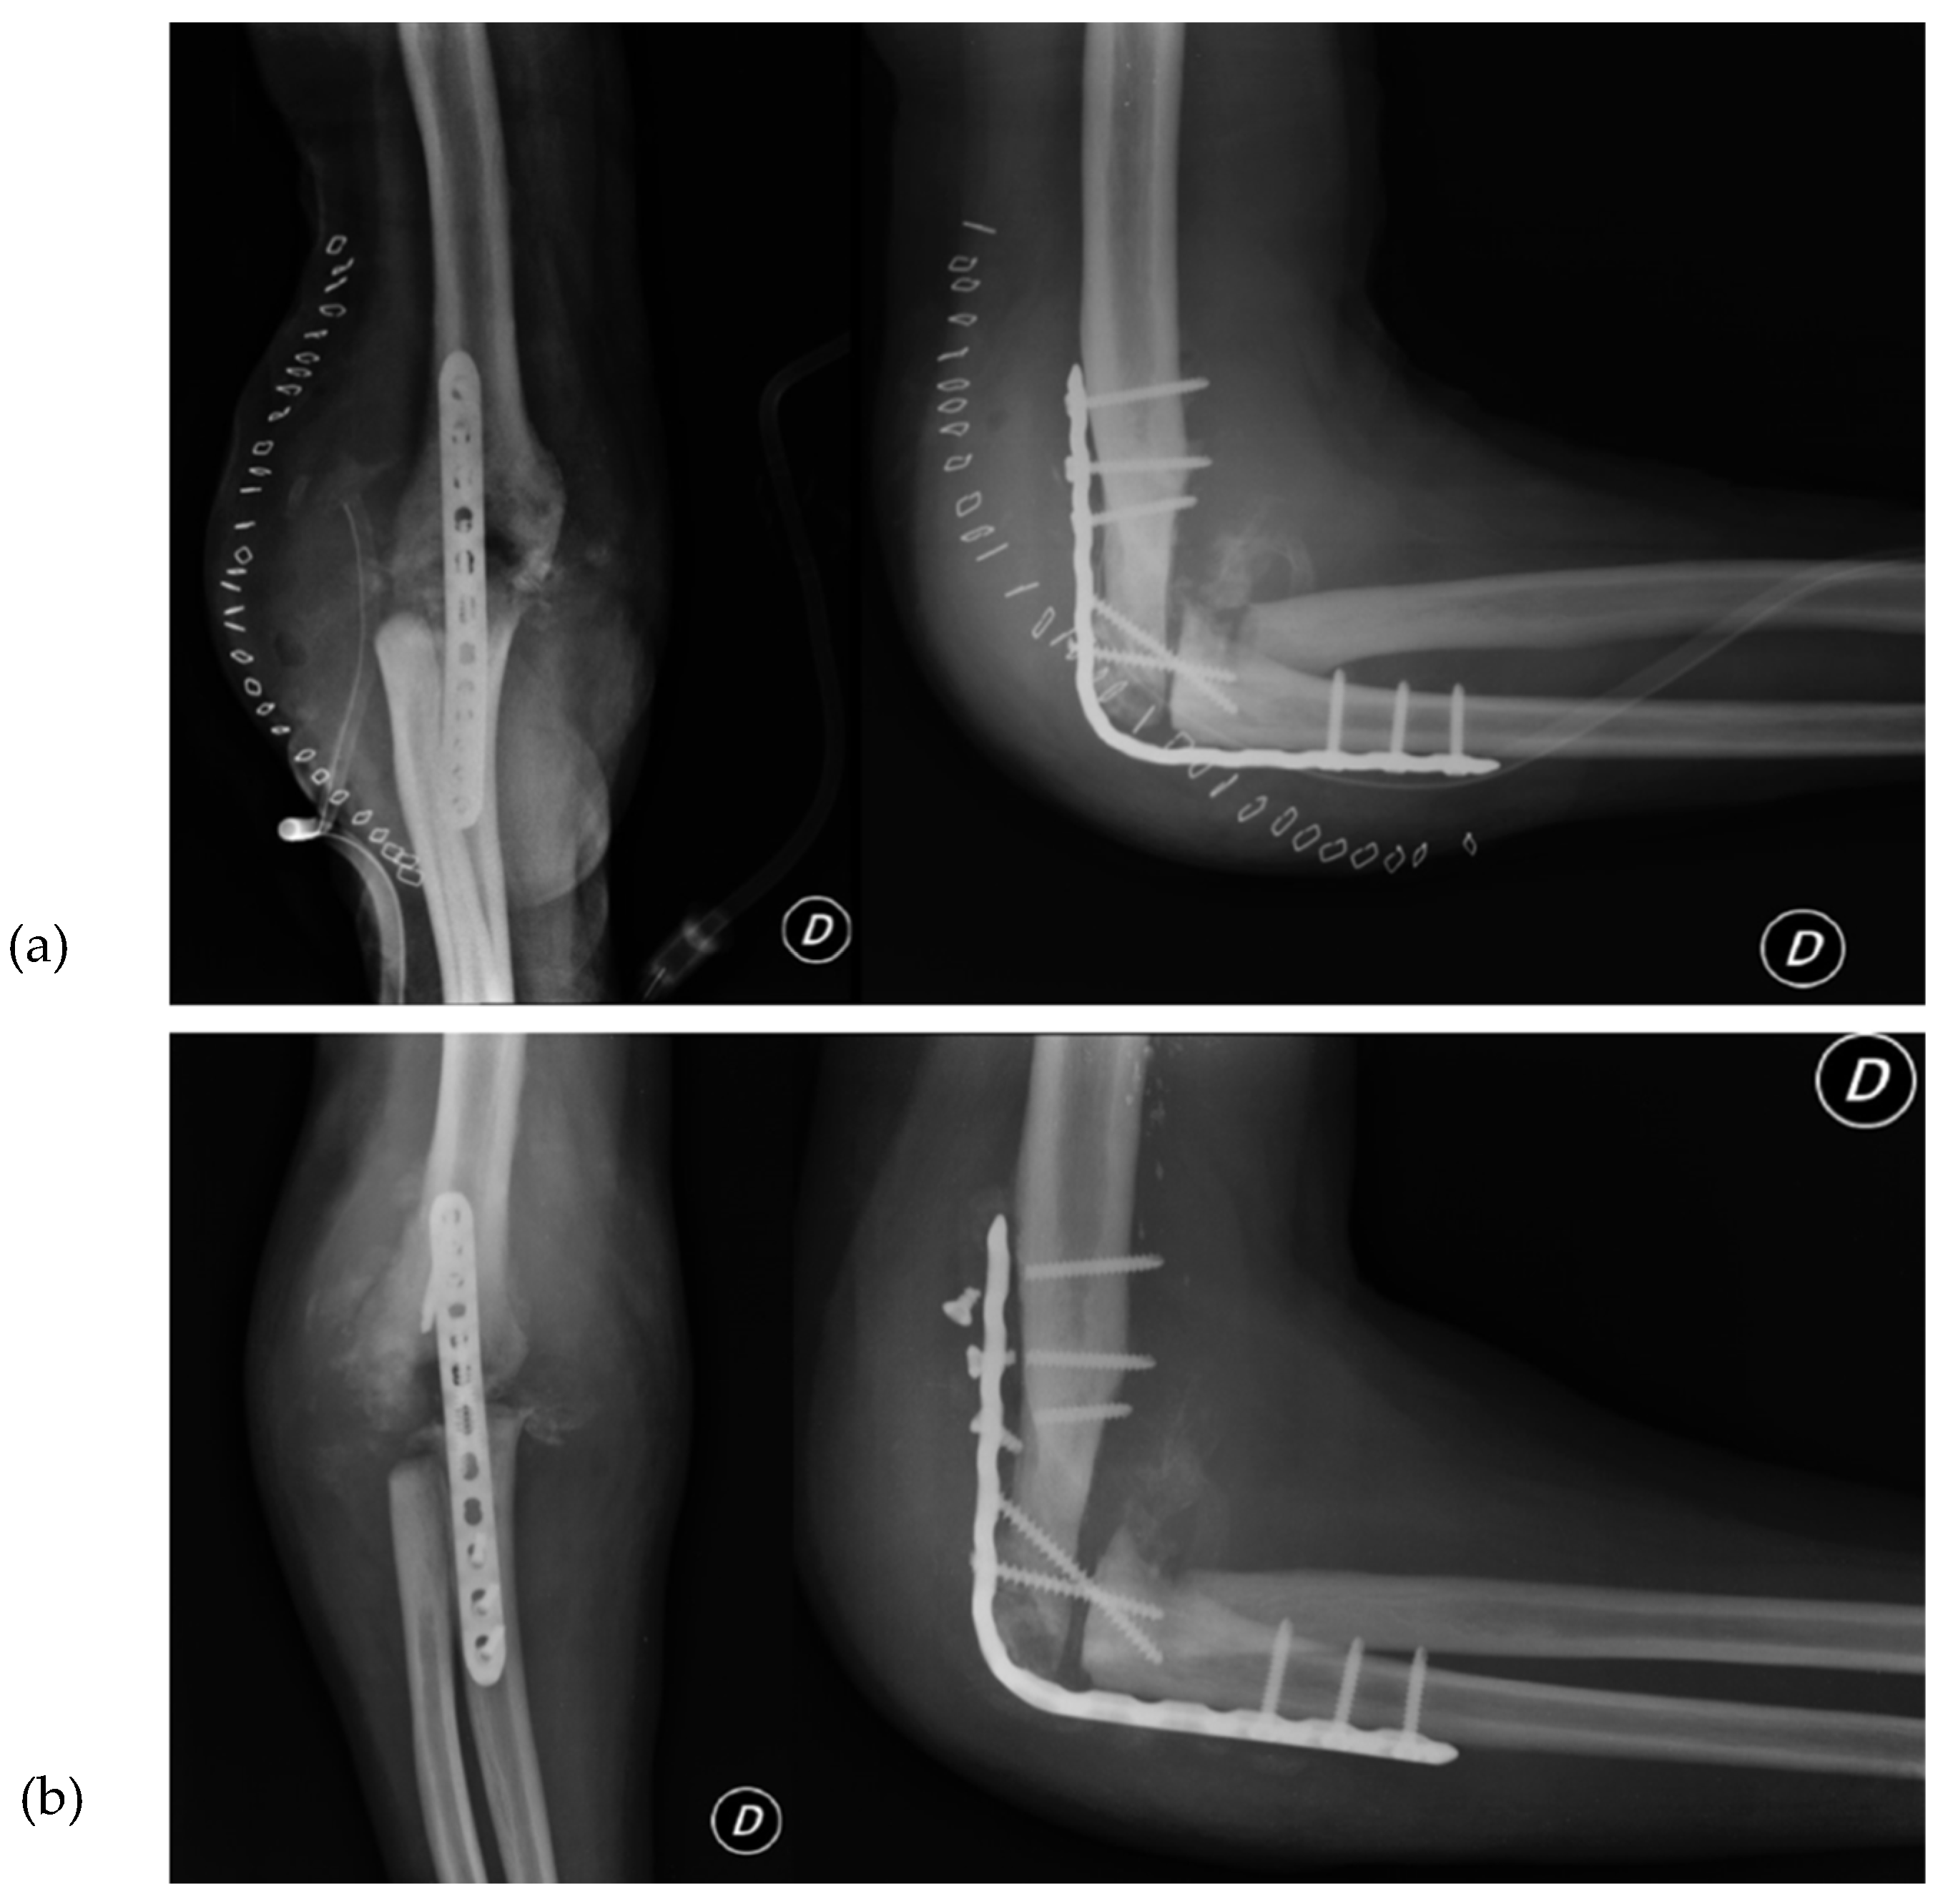

Due to the patient's clinical symptoms, a right elbow X-ray was performed (Figure 1), which revealed significant morpho-structural changes in the bone structures of the joint, with osteolytic areas of bone. The X-ray also showed calcification of the periarticular soft tissue and dislocation of the radial head. Additionally, the patient had an enlarging ulnar elbow mass, which was attributed to recurrent intra-articular bleeding that involved the periarticular soft tissue.

Figure 1. X-Ray anteroposterior and lateral views of the right elbow. First radiological presentation.